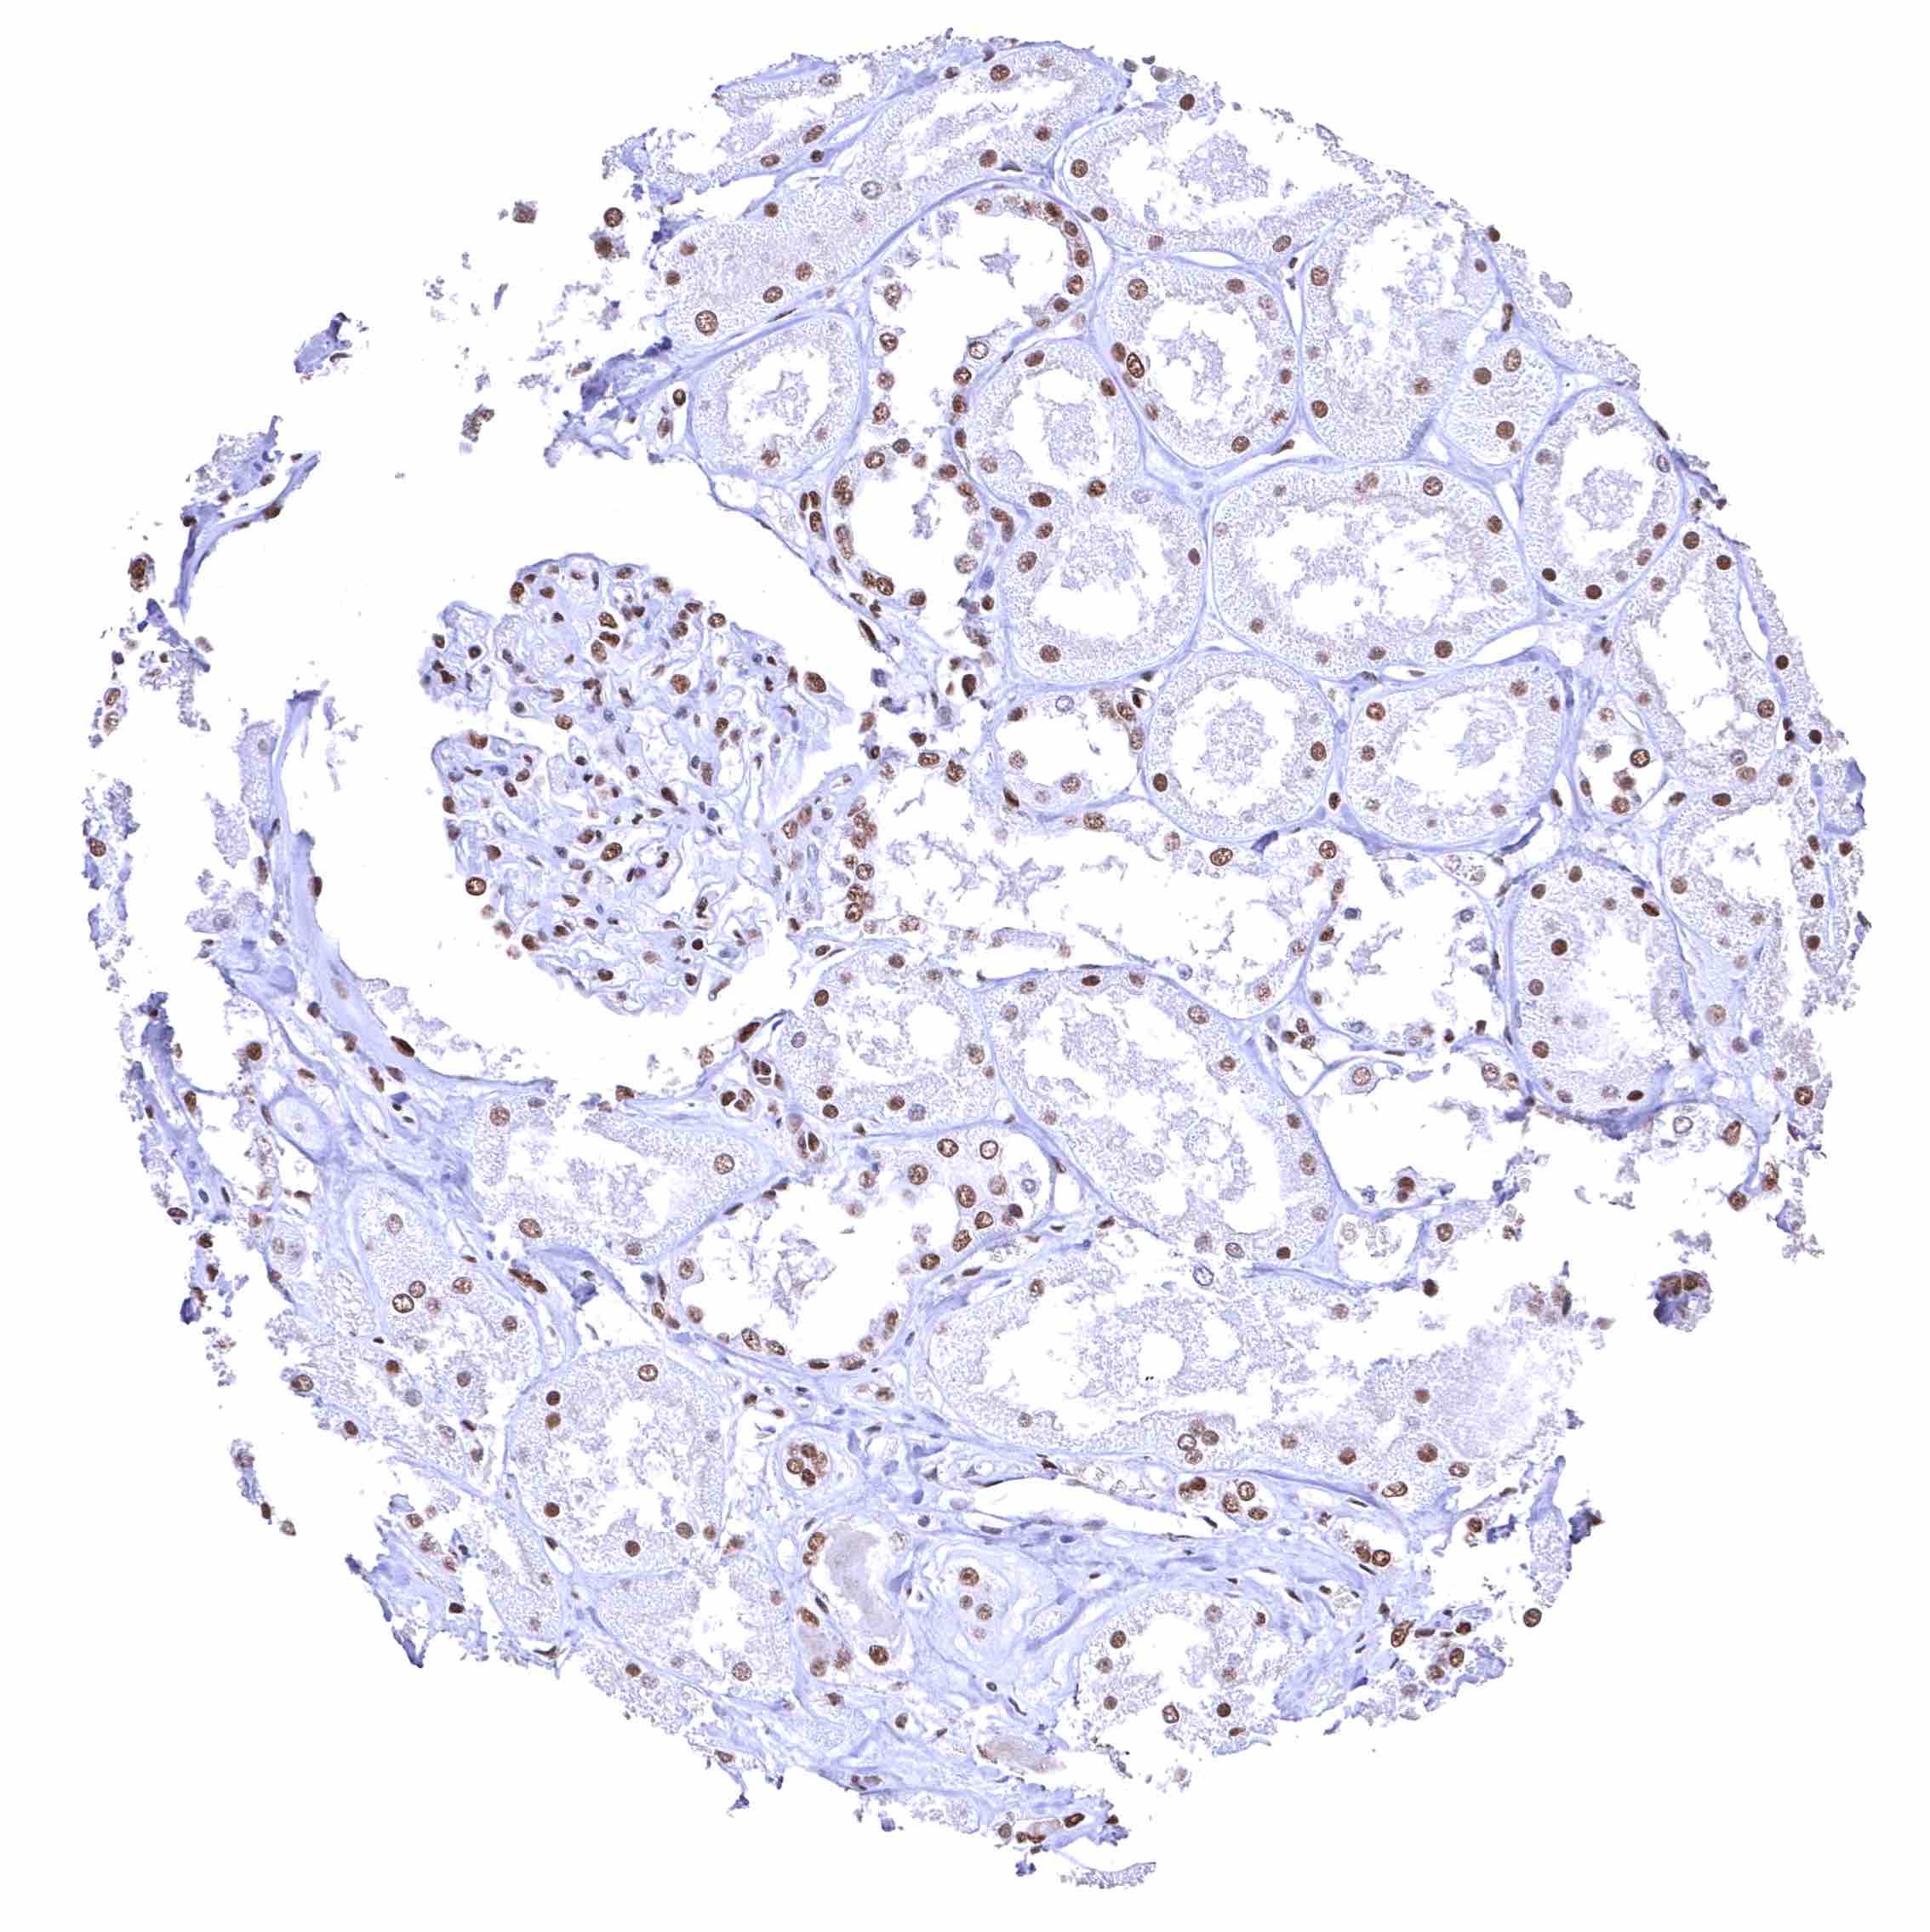

Testis – The level of nuclear BRD4 staining decreases with maturation of germ cells.